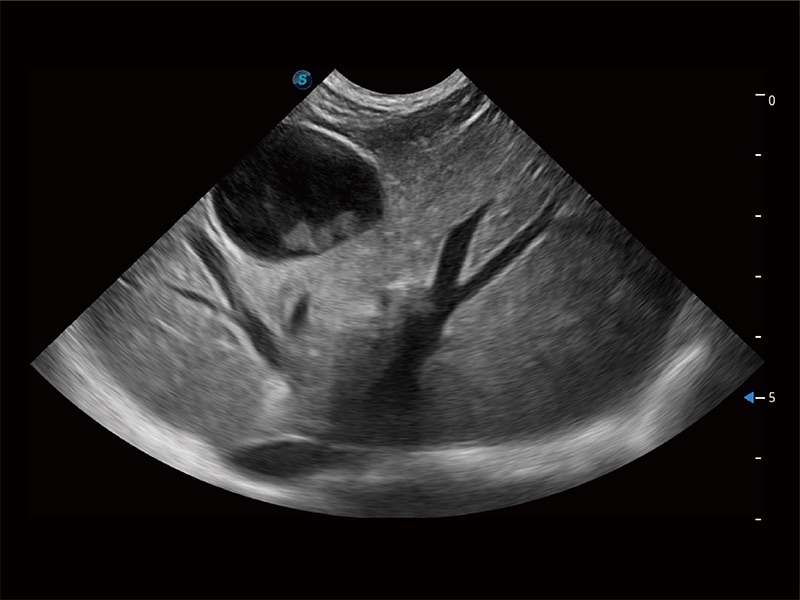

(犬)胎儿四腔心

(犬)肝脏

(猫)胆囊

(犬)肠道